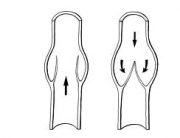

| 07:58, 15 בנובמבר 2012 | וריד215.png (קובץ) |  |

10 קילו־בייטים | Motyk | 1 | |